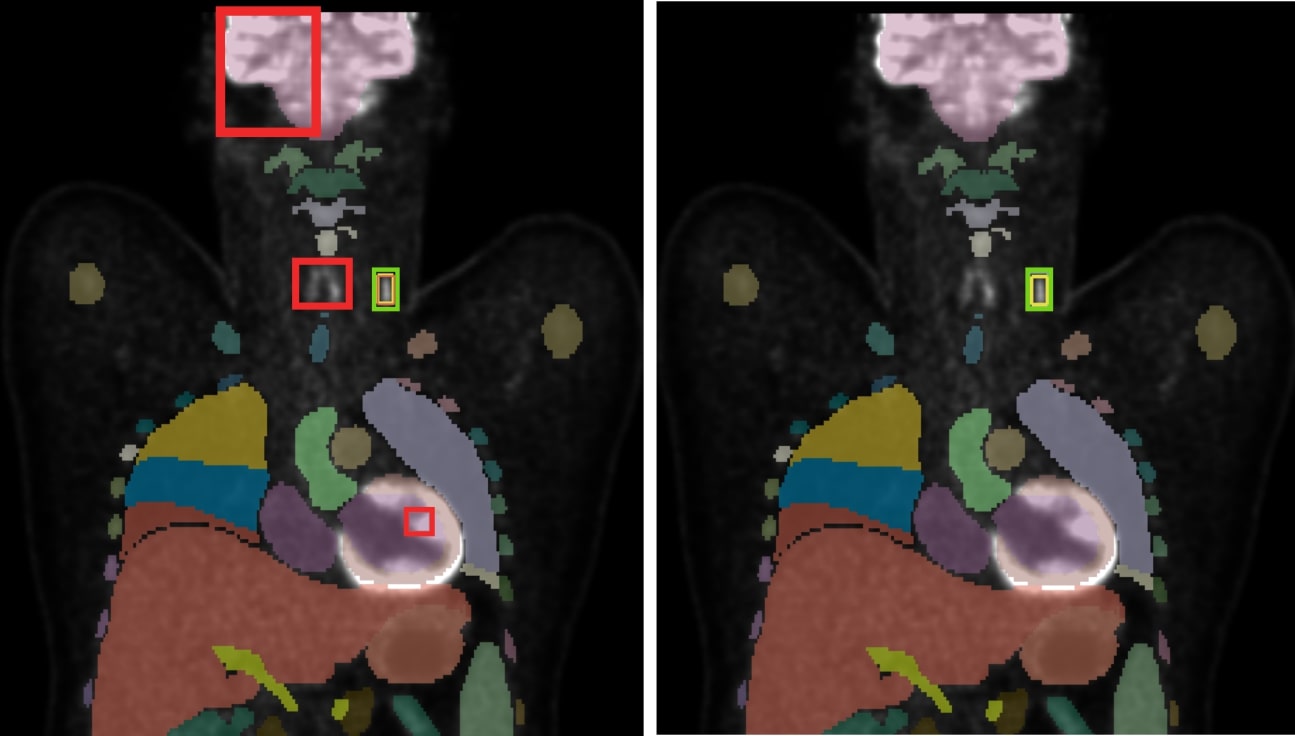

Experimental results demonstrated that the inclusion of anatomical information led to improved performance, particularly in the nnDetection framework. These findings suggest that the network is capable of learning contextual anatomical information, correlating the occurrence of lymphoma lesions with specific organs, while also learning to ignore physiologically high-uptake regions in PET, such as the liver, thyroid, brain, and bladder, as shown in Figure 12. This performance boost is likely attributable to the regionally localized nature of convolutional filters used in nnDetection, which appear to benefit from the explicit anatomical context provided.

Figure 12: Visualization of detection results: baseline nnDetection (left) vs. enhanced nnDetection (right) with Total Segmentator mask overlay. The incorporation of anatomical information in the enhanced model demonstrates a reduction in false positive detections, particularly evident in the brain, thyroid, and heart regions.